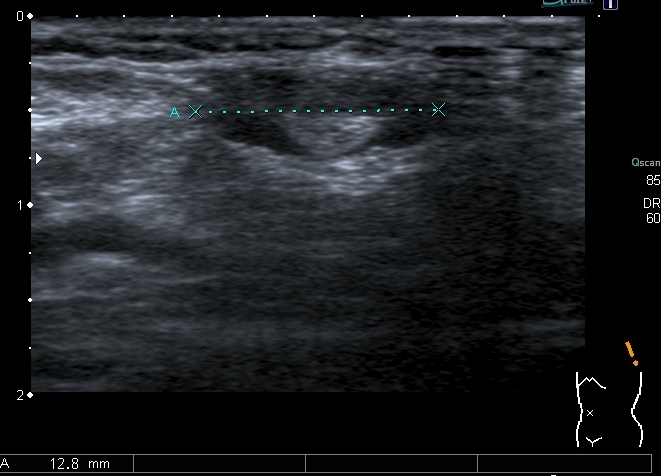

Левый подмышечный узел

2. Распространённая лимфаденопатия, хотя "плохим" выглядит только лимфатический узел справа в подмышечной впадине, но есть лимфатические узлы до 12 - 15 мм и в левой подмышечной области , и подчелюстные лимфатические узлы